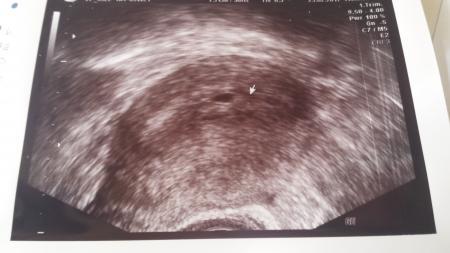

Hallo ihr lieben. Mich würde mal interessieren ob ihr 1 oder 2 Fruchthöhlen seht:-) Bin erst 6 ssw.ist nur Neugier

Bild zu Was seht ihr? - Schwanger - wer noch? Rund um die Schwangerschaft

Also ich würde zwei sagen. Hat dein arzt denn nichts dazu gesagt :)?

Ich sehe zwei

Zwei FruchtHöhlen ... sah bei mir auch so aus am Anfang!!! Herzlichen Glückwunsch!!!

Sieht aus wie ein trauriger smiley Also ich sehe auch zwei fruchthöhlen!

Ich seh auch zwei. Zwillinge.. Ich hoff, ich bekomm auch irgendwann welche. Wünsche ich mir schon seitdem ich klein bin. Find das immer so süß.